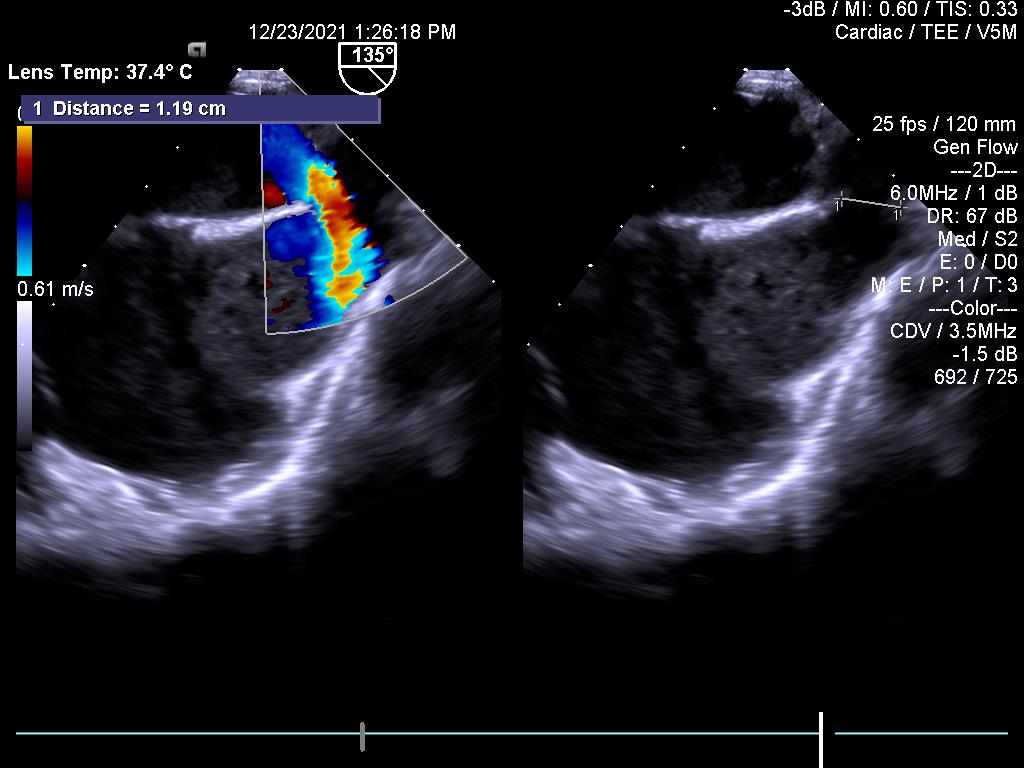

7.Dẫn đường hỗ trợ nong van hai lá bằng bóng

Trước nong van:

Sau nong van: